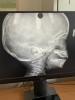

Можно ли определить степень аденоидов по снимку?

Девочки, а по снимку можно определить степень аденоидов? Посмотрите, пожалуйста 🙏 к врачу только в понедельник

Снимок в комментариях